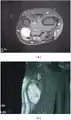

- Pleural schwannoma is extremely rare. A unique subtype of schwannoma that typically develops in superficial (cutaneous or subcutaneous) sites and may be identified by its development pattern, which is plexiform (intraneuralnodular)[7][8].The correlation with schwannoma predisposition disorders like NF2 and schwannomatosis, however, is minimal (approximately 5 percent of cases)[9].These tumors might lack a capsule or be less encapsulated than a typical schwannoma.More challenging to identify from MPNST are the infrequent plexiform schwannomas that develop in deep anatomical sites, such as soft tissue[10] or major peripheral nerves.[11] These tumors may exhibit enhanced cellularity and mitotic activity. Although the likelihood of these tumors developing into cancer is extremely low, local recurrence is possible in around half of cases. On MRI, it usually shows hyper or iso-intensity on T1-weighted images and heterogenous hyperintensities on T2 weighted images. Pleural schwannoma typically shows fatty degeneration, hemorrhage, perivascular hyalinization, and cystic formation thus giving heterogenous hyperintensities on T2 weighted images. Complete surgical removal of pleural schwannoma is the usual treatment.[12]

- MRI showing schwannoma of ulna nerve